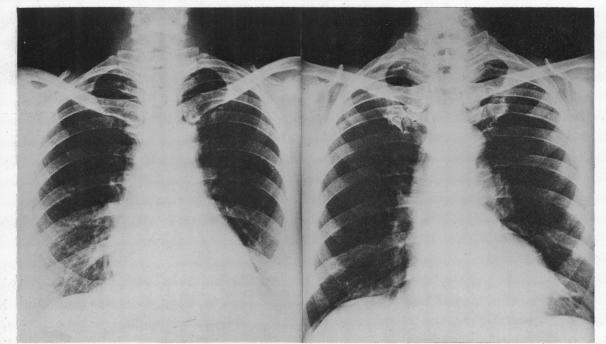

THE HEART IN RHEUMATOID ARTHRITIS.

Br Heart J. 1948 Apr;10(2):125-34. doi: 10.1136/hrt.10.2.125.